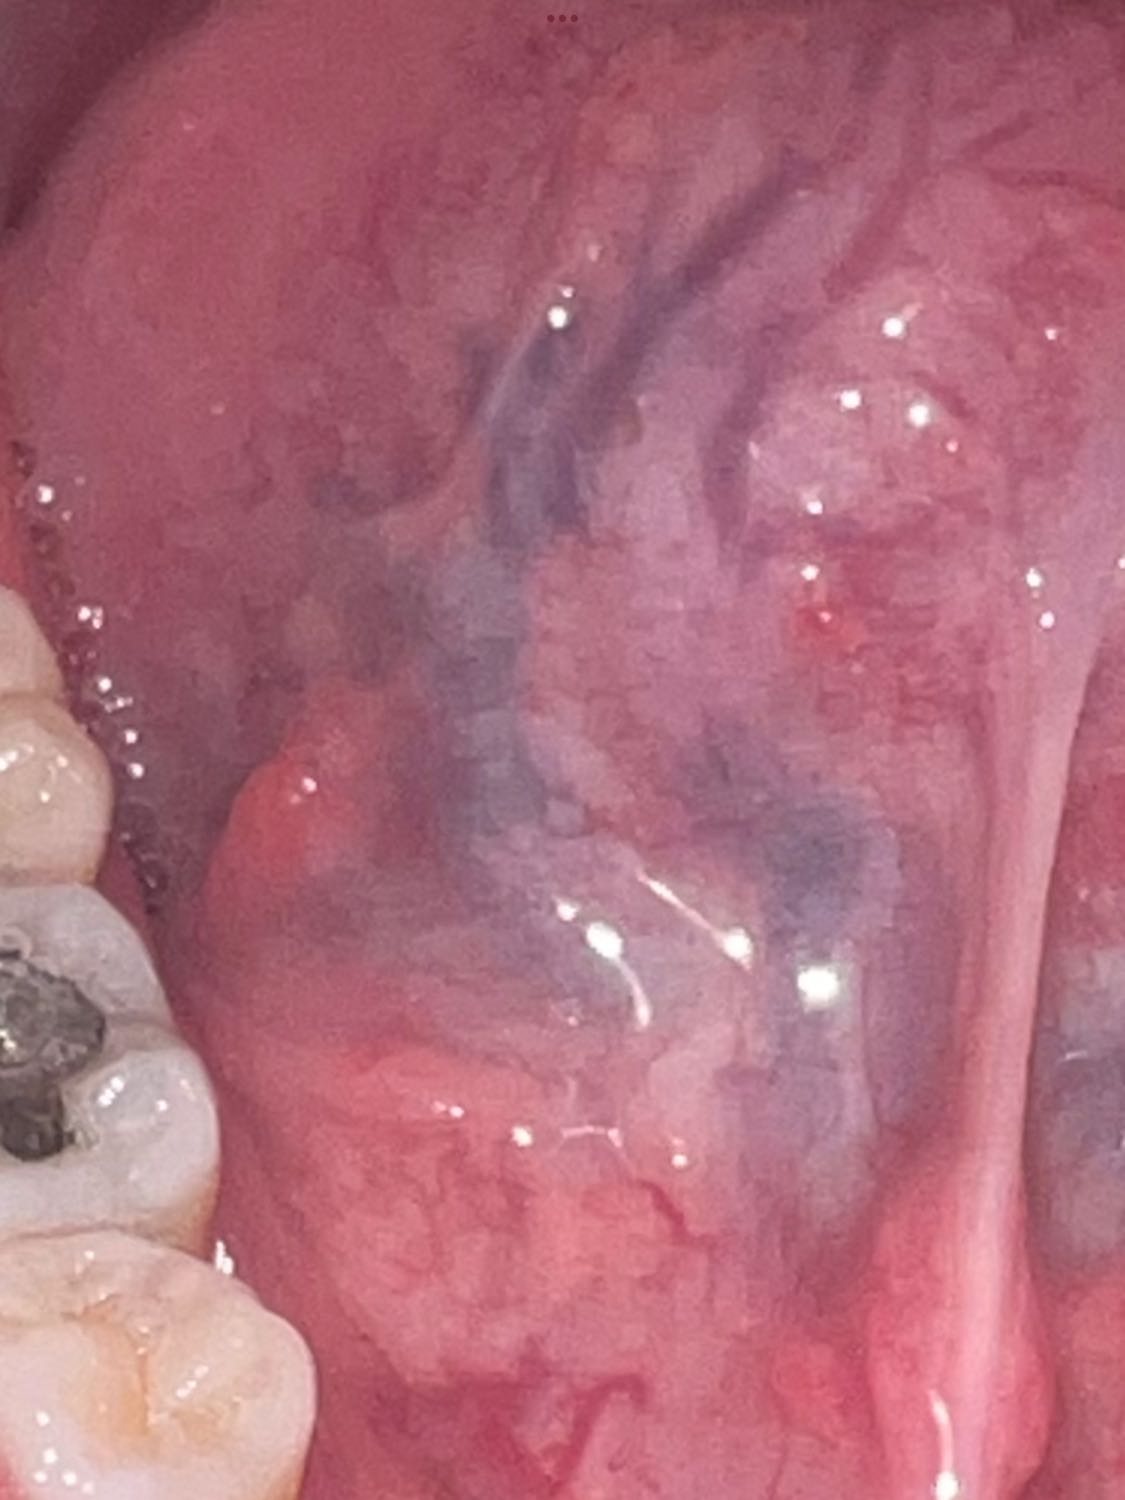

มีตุ่มสีแดงใต้ลิ้นยื่นออกมามีความเจ็บๆระคายเคืองจะเป็นอะไรไหมคะ🙏🏻🥹